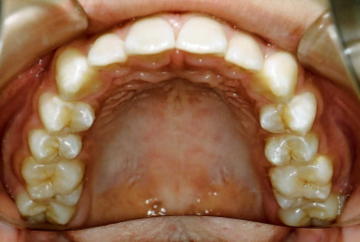

上の写真は、私(院長)の子供が12歳の時の写真です。

乳歯列の時を含めてむし歯ゼロです。